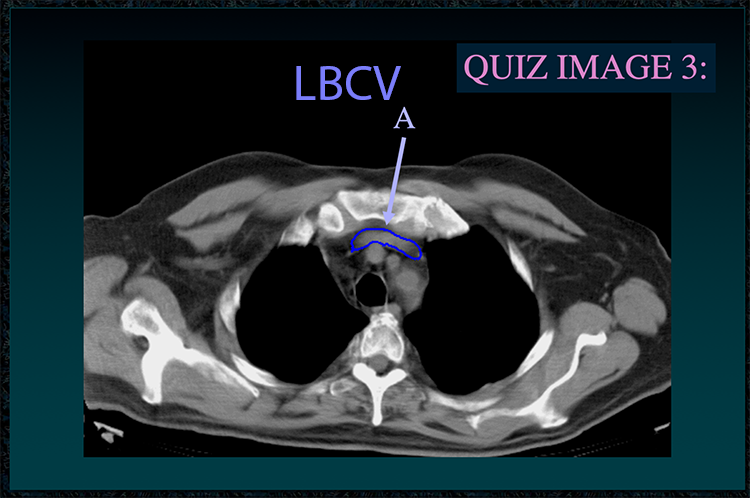

◂Chest Anatomy Review